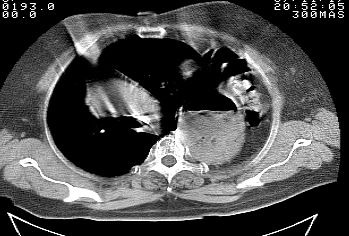

标题: CT10753:女, 64岁 隔疝 [打印本页]

标题: CT10753:女, 64岁 隔疝

女, 64岁 三十年前胸部外伤史, 间断胸闷,

典型左侧膈疝,疝出物为胃和大网膜,纵隔右移

同意左侧膈疝,不过,有过外伤史,左肺有受压征象,同时有胸膜增厚。